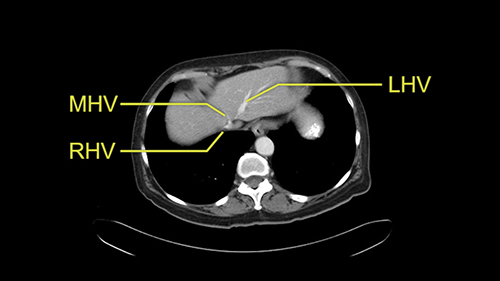

The procedure-specific slowing down moments from a technical point of view for a right hemihepatectomy include a careful evaluation of the inflow structures including the right hepatic artery, the right portal vein, as well to make sure that I have identified and preserved the left hepatic artery and the left portal vein at all times, and minimize any injury or dissection of the common bile duct. Also, I am careful when I mobilize the right liver, not to tear the right triangular ligament and cause bleeding of the liver as I mobilize it off the retroperitoneum and the bare area. In addition, the last procedure-specific slowing down moment is to carefully identify the right hepatic vein and ensure that I encircle it safely without damaging the IVC or the middle and left hepatic vein structures at all times.

So when doing a major liver resection, obviously we would focus on a few issues. The first is hepatic parenchyma: is there adequate liver, residual liver and orientation and ratio of the right to left lobe here is pretty normal. It looks like its about 60:40 or 70:30, and because its only a right lobe, I probably wouldn’t do any volumes assuming she has normal liver function which I think she does. The only additional feature of interest is that she has received chemotherapy and one can see the effect of chemotherapy on the density of the liver but again, it doesn’t usually cause significant problems with a short course of neoadjuvant chemotherapy, or liver failure.

So I would then focus on the hepatic outflow because that’s the way we do the operation is by mobilizing the liver. So the vena cava looks quite normal. The right hepatic vein looks quite normal. There are no large additional outflow veins from the right lobe which would generate slowing down moments. The hepatic artery is unremarkable and is not usually an issue we can define the anatomy quite clearly at surgery.

Coming up a little bit higher. There’s a little bit of biliary dilatation as well. On the right side of the liver. Which may be nothing but it may be an indicator or harbinger of nodal disease in the hepatoduodenal ligament so something to be aware of. If the enzymatic liver function tests are normal and there’s no evidence of a stone in the common bile duct on cross sectional imaging you wouldn’t need to do anything about it but just to be aware of that.![[RHV]](jpg/preop_as_p4.jpg)

So we’re going through the liver segments now. Here we’ve got the inflow; here’s the main portal vein, right anterior sectoral portal vein, right posterior sectoral portal vein there. Here’s the main here going to the left lobe first of all. So that’s 3 and 2 there, they look clear, and there’s a good size of the left lobe with a good girth. So 3 and 2 look clear. There are usually more feedback branches from the left portal vein to segment 4b but that also looks relatively clear. There’s a little more disease over on the right side there. So that would be...right hepatic vein here...that’s Segment 7. So we’ve got disease in 7, 5, probably in 6 on the right side; at least 3 lesions. That’s the distribution of the lesions.![[Ant. RPV] [Main PV] [Post. RPV]](jpg/preop_as_p5.jpg)